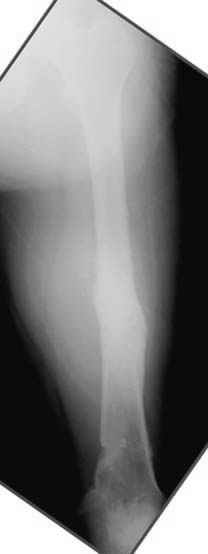

Несколько снимков из моей коллекции, чтобы разьяснить, почему мы до сих пор делаем различные варианты остеотомии.

N3 рисунок окончательный снимок, после операции моя рентгенограмма должен выглядеть примерно как эта картина. На N4 снимке клин перед удалением; N5 послеоперации 3 нед.; N6 окончательная рентгенограмма.

Отправитель: Djoldas Kuldjanov 23 Ноябрь 2004, 18:21

пластическая модель; и коррекция бедра аппаратом Илизарова.

Узкий к-м канал - тонкий гвоздь- усталостный перелом дистальных винтов - развитие нестабильности и как ее результат остеолиз вокруг гвоздя - деформация анатомической оси бедра. Похоже, что я понял почему аппарат, а не новый гвоздь:-)

ЕТ - Изначально костно-мозговой канал бедра был узкий, дальнейшее его рассверливание ещё больше скомпрометирует прочность бедра( латеральный кортекс дистального отломка уже истончен), приведет к дефекту наружной стенки - хотя это только мои догадки - хотелось бы знать мнение Джолдаса о выбранной тактике.